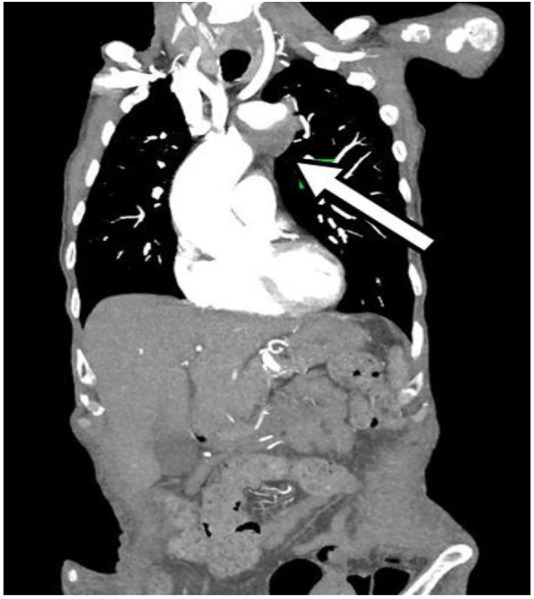

我们报告一例85岁男性膀胱腺癌病史,经17次膀胱内灌注卡介苗(BCG)治疗,表现出体质症状和多发假性动脉瘤:左侧锁骨下动脉、右侧髂外动脉和右侧股浅动脉。尽管没有最初的微生物学发现,血液和尿液培养最终培养出对吡嗪酰胺耐药的牛分枝杆菌BCG菌株。在微生物学证实之前,临床病程以进行性恶化和死亡为标志。本病例突出了膀胱内卡介苗治疗的一种罕见但严重的并发症,并强调了在卡介苗暴露后出现不明原因假性动脉瘤的患者早期怀疑和联合手术和抗菌治疗的重要性。